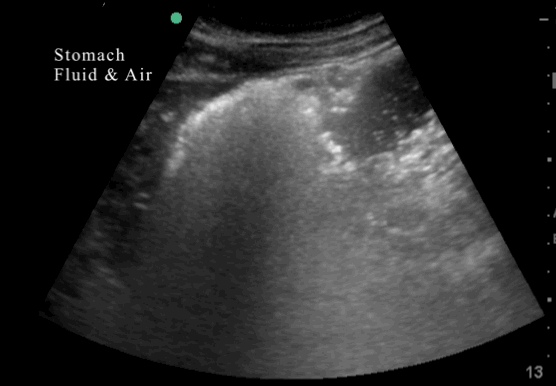

- Is the stomach empty or full ?

- If clear fluid is present in the stomach – calculating the volumen in the stomach

- Does the content in the stomach represent a risk for the patient ?